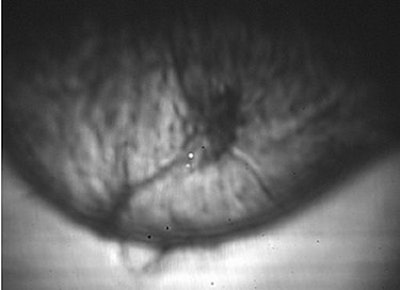

DUS uses a gray scale that correlates white with high sound transmission and dark with low sound transmission, making cysts look relatively white and solid masses look dark.

A fibroademona (above) and a ductal carcinoma (middle) as seen on diffractive ultrasound. Below, normal findings that highlight the different tissue layers in the breast. Images courtesy of Advanced Imaging Technologies.

On DUS, cystic lesions are round, oval, or lobular in shape, with circumscribed margins. Solid masses are oval, lobulated, or irregular in shape, with either circumscribed or ill-defined margins. Malignant tumors exhibit architectural distortion by distorting the pattern produced by the surrounding fibroglandular tissue.

"It’s a promising technique insofar as differentiating cysts and solid masses. If it’s dark on DUS we know it’s solid. But whether it’s benign or not we can’t tell," Hashimoto said.